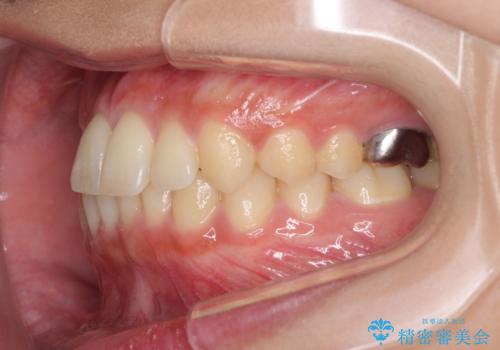

海外勤務中のインビザラインによる矯正治療

- 前歯のクロスバイトを気にして来院され患者様です。

定期的に日本には帰国するものの、日ごろは海外でお仕事をされているとのことで、インビザラインによる治療を希望されました。

トラブルが起こった時に対応ができない、来院を帰国のタイミングに合わせなければならないため治療が長期化するなど困難はありますが、ワイヤー矯正と比べると治療を進めやすいといったメリットがあるので、インビザラインにて矯正治療を行うこととしました。

治療期間が世界的な感染症の流行時期と重なったため、海外と日本での往来が困難となり、治療継続が懸念されました。

それでも、しっかりとマウスピースを装着してくださったので、大きなトラブルもなく治療を終えることができました。